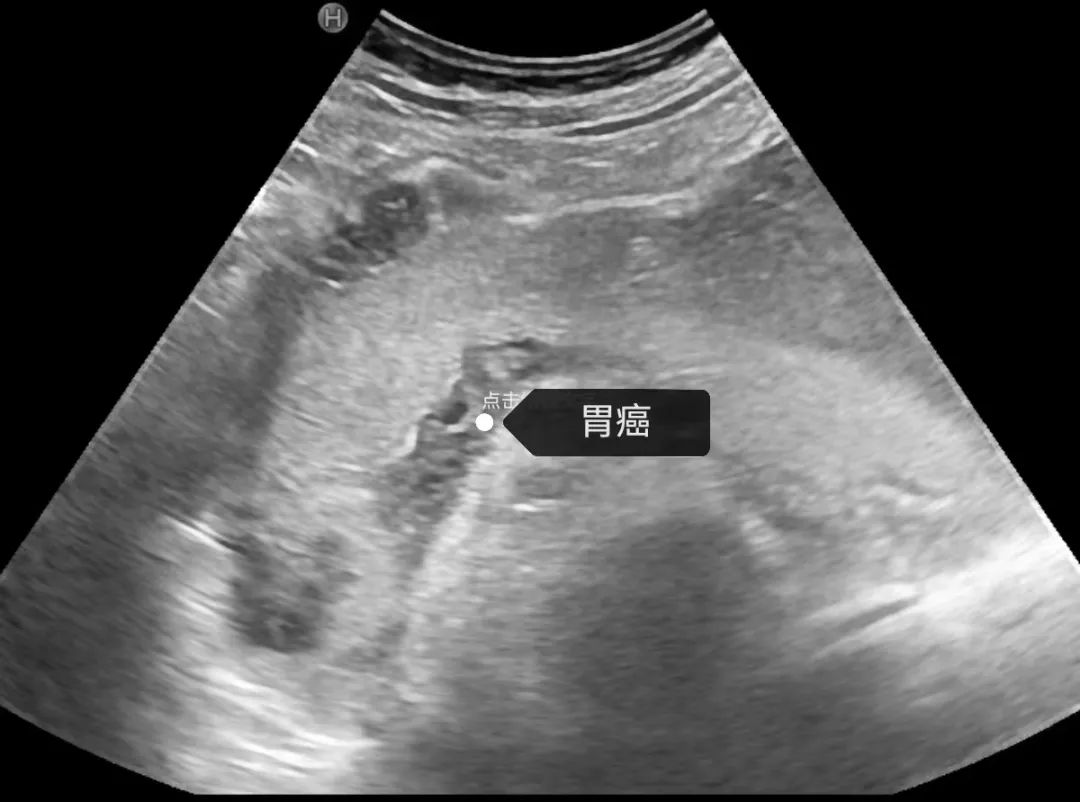

1.肿瘤性病变:如:胃息肉、平滑肌瘤、胃癌等。

典型病例分享